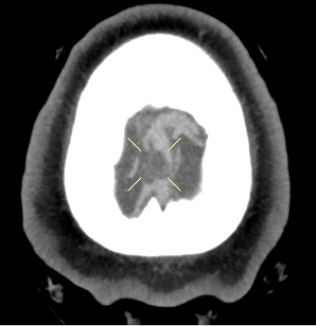

Diagnostic Testing. The patient’s CT brain imaging revealed a small amount of air in both frontal horns of the lateral ventricles (Figure 1). Her brain CTA revealed distension of the superior sagittal sinus (SSS), inferior sagittal sinus, transverse sinus, and vein of Galen and an extra-axial SSS defect (Figures 2-4). The initial report of the MRI brain with and without contrast redemonstrated trace pneumocephalus but was otherwise unremarkable. Later review after 10 days, revealed pachymeningeal enhancement, venous sinus distension, and a filling defect in the SSS suggestive of venous sinus thrombosis (Figures 5, 6). Her MRI of the cervical spine did not reveal another cause of neck pain, and her urine protein was negative.

Fig. 4. Axial view of the focal filling defect compatible with thrombus within the superior sagittal sinus.